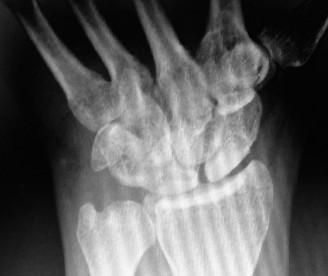

The same patient is seen in clinic 4 weeks later and still has persistent pain. An x-ray ordered at this time reveals the findings shown (Fig. 3–2). What is the more prudent thing to do next?

Figure 3–2(©) Sunil Thirkannad and Christine M. Kleinert.

The correct answer is (A). The x-ray reveals a fracture of the scaphoid. Healing rates are around 75% with nonsurgical treatment in adults compared to around 95% after surgery. However, since the patient is a 14-year-old child and has already been in a splint for 4 weeks, a prudent course would be to continue splinting for a further 2 to 4 weeks.